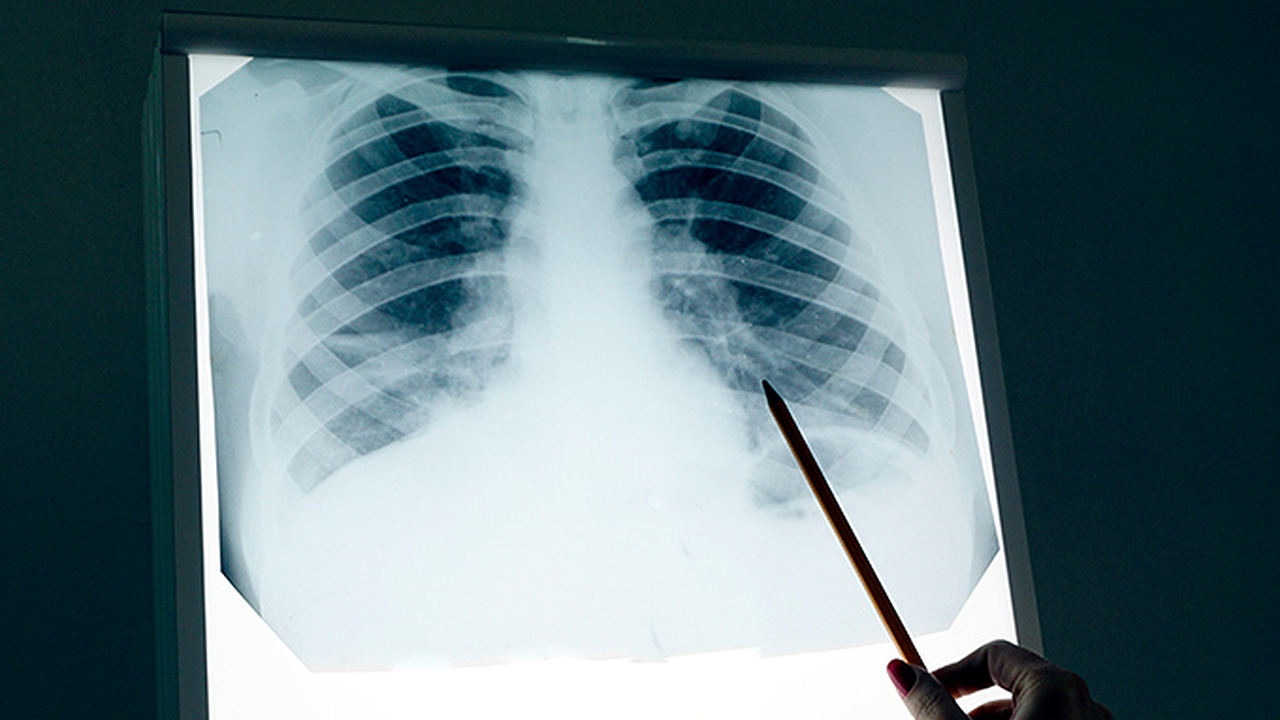

肺炎支原体阳性可能引发呼吸道感染,严重时可导致肺炎、支气管炎等并发症。肺炎支原体感染主要通过飞沫传播,常见症状包括咳嗽、发热、咽痛等,部分患者可能出现胸痛、呼吸困难等表现。

少数情况下,肺炎支原体感染可能引发严重并发症。患者可能出现大叶性肺炎,表现为高热、剧烈咳嗽、胸痛等症状。个别患者可能发生胸腔积液,导致呼吸困难加重。免疫功能低下者可能出现重症肺炎,甚至需要住院治疗。儿童患者可能出现喘息、气促等表现,严重时可能影响正常活动。